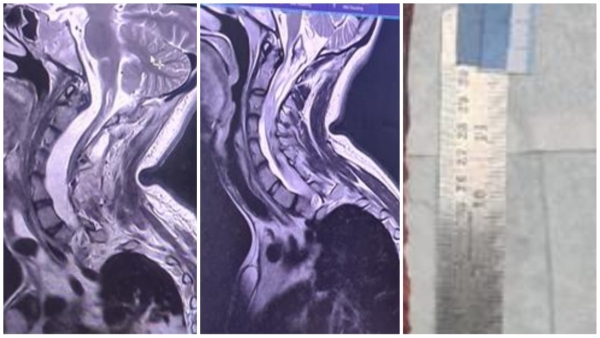

एक 22 वर्षीय महिला अपने चारों अंगों में कमजोरी के साथ न्यूरोसर्जरी ओपीडी में आई और उसे संपूर्ण मूल्यांकन के लिए भर्ती कर लिया गया। रेडियोलॉजी विभाग में पूरी रीढ़ की हड्डी का एमआरआई किया गया और डॉ राधा गुप्ता एवं डॉ हर्षा से चर्चा की गई।

एमआरआई में एक इंट्रामेडुलरी ट्यूमर दिखा जो सर्विकोमेडुलरी जंक्शन से डी 11 वर्टिब्रा तक फैला हुआ था। यह अधिक चुनौतीपूर्ण था क्योंकि मरीज को स्कोलियोसिस था।

केस का संचालन डॉ सुमित राज ने किया, केस में सहयोग डॉ जितेंद्र और डॉ अभिषेक ने किया। सर्वाइकल से डी12 वर्टिब्रा तक लैमिनोटॉमी की गई। ट्यूमर को पूरी तरह से काट दिया गया और 15 घंटे तक चले ऑपरेशन में मामला ख़त्म हो गया। यह ट्यूमर करीब 40 सेंटीमीटर तक लंबा था। ट्यूमर हटाने के बाद स्पाइन लैमिनोटॉमी को मिनी प्लेट और स्क्रू से ठीक किया गया। न्यूरो ओट स्टाफ का सहयोग अनुकरणीय था, विशेषकर नीनू, भगवती, नंदराम और अन्य का।